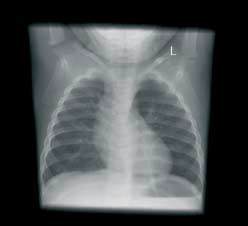

Immagini di alta qualità. Bassi dosaggi. Flusso di lavoro efficiente. DX-G: un livello a parte.